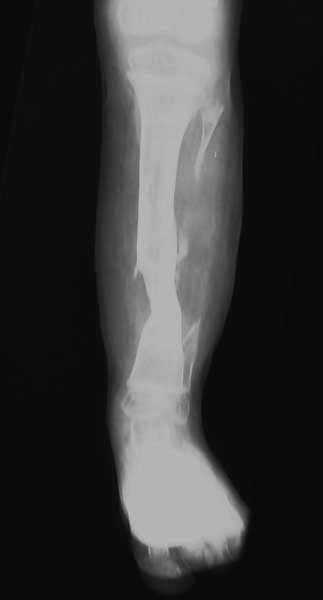

Хочу поделиться с вами опытом недавно пролеченного мною мальчика пяти лет с врождённым псевдартрозом. В начале ему была пересаженна малоберцовая кость. Операцию проводили с пластическими хирургами. Шесть месяцев спустя малоберцовка прирослась и мальчик начал ходить в специальном бондаже. Через некоторое время в следствии не аккуратности родителей(ктото сел на ногу ребёнка)произошёл перелом на уровне стыка. Попытка сростить наложив аппарат была не удачной.Поэтому было принято решение удолить пересаженную малоберцовую кость и заместить дефект за щёт верхней кортикотомии. Срок лечения один год. Был достигнут положительный результат. Спустя полтора года повторного перелома не наблюдалось.